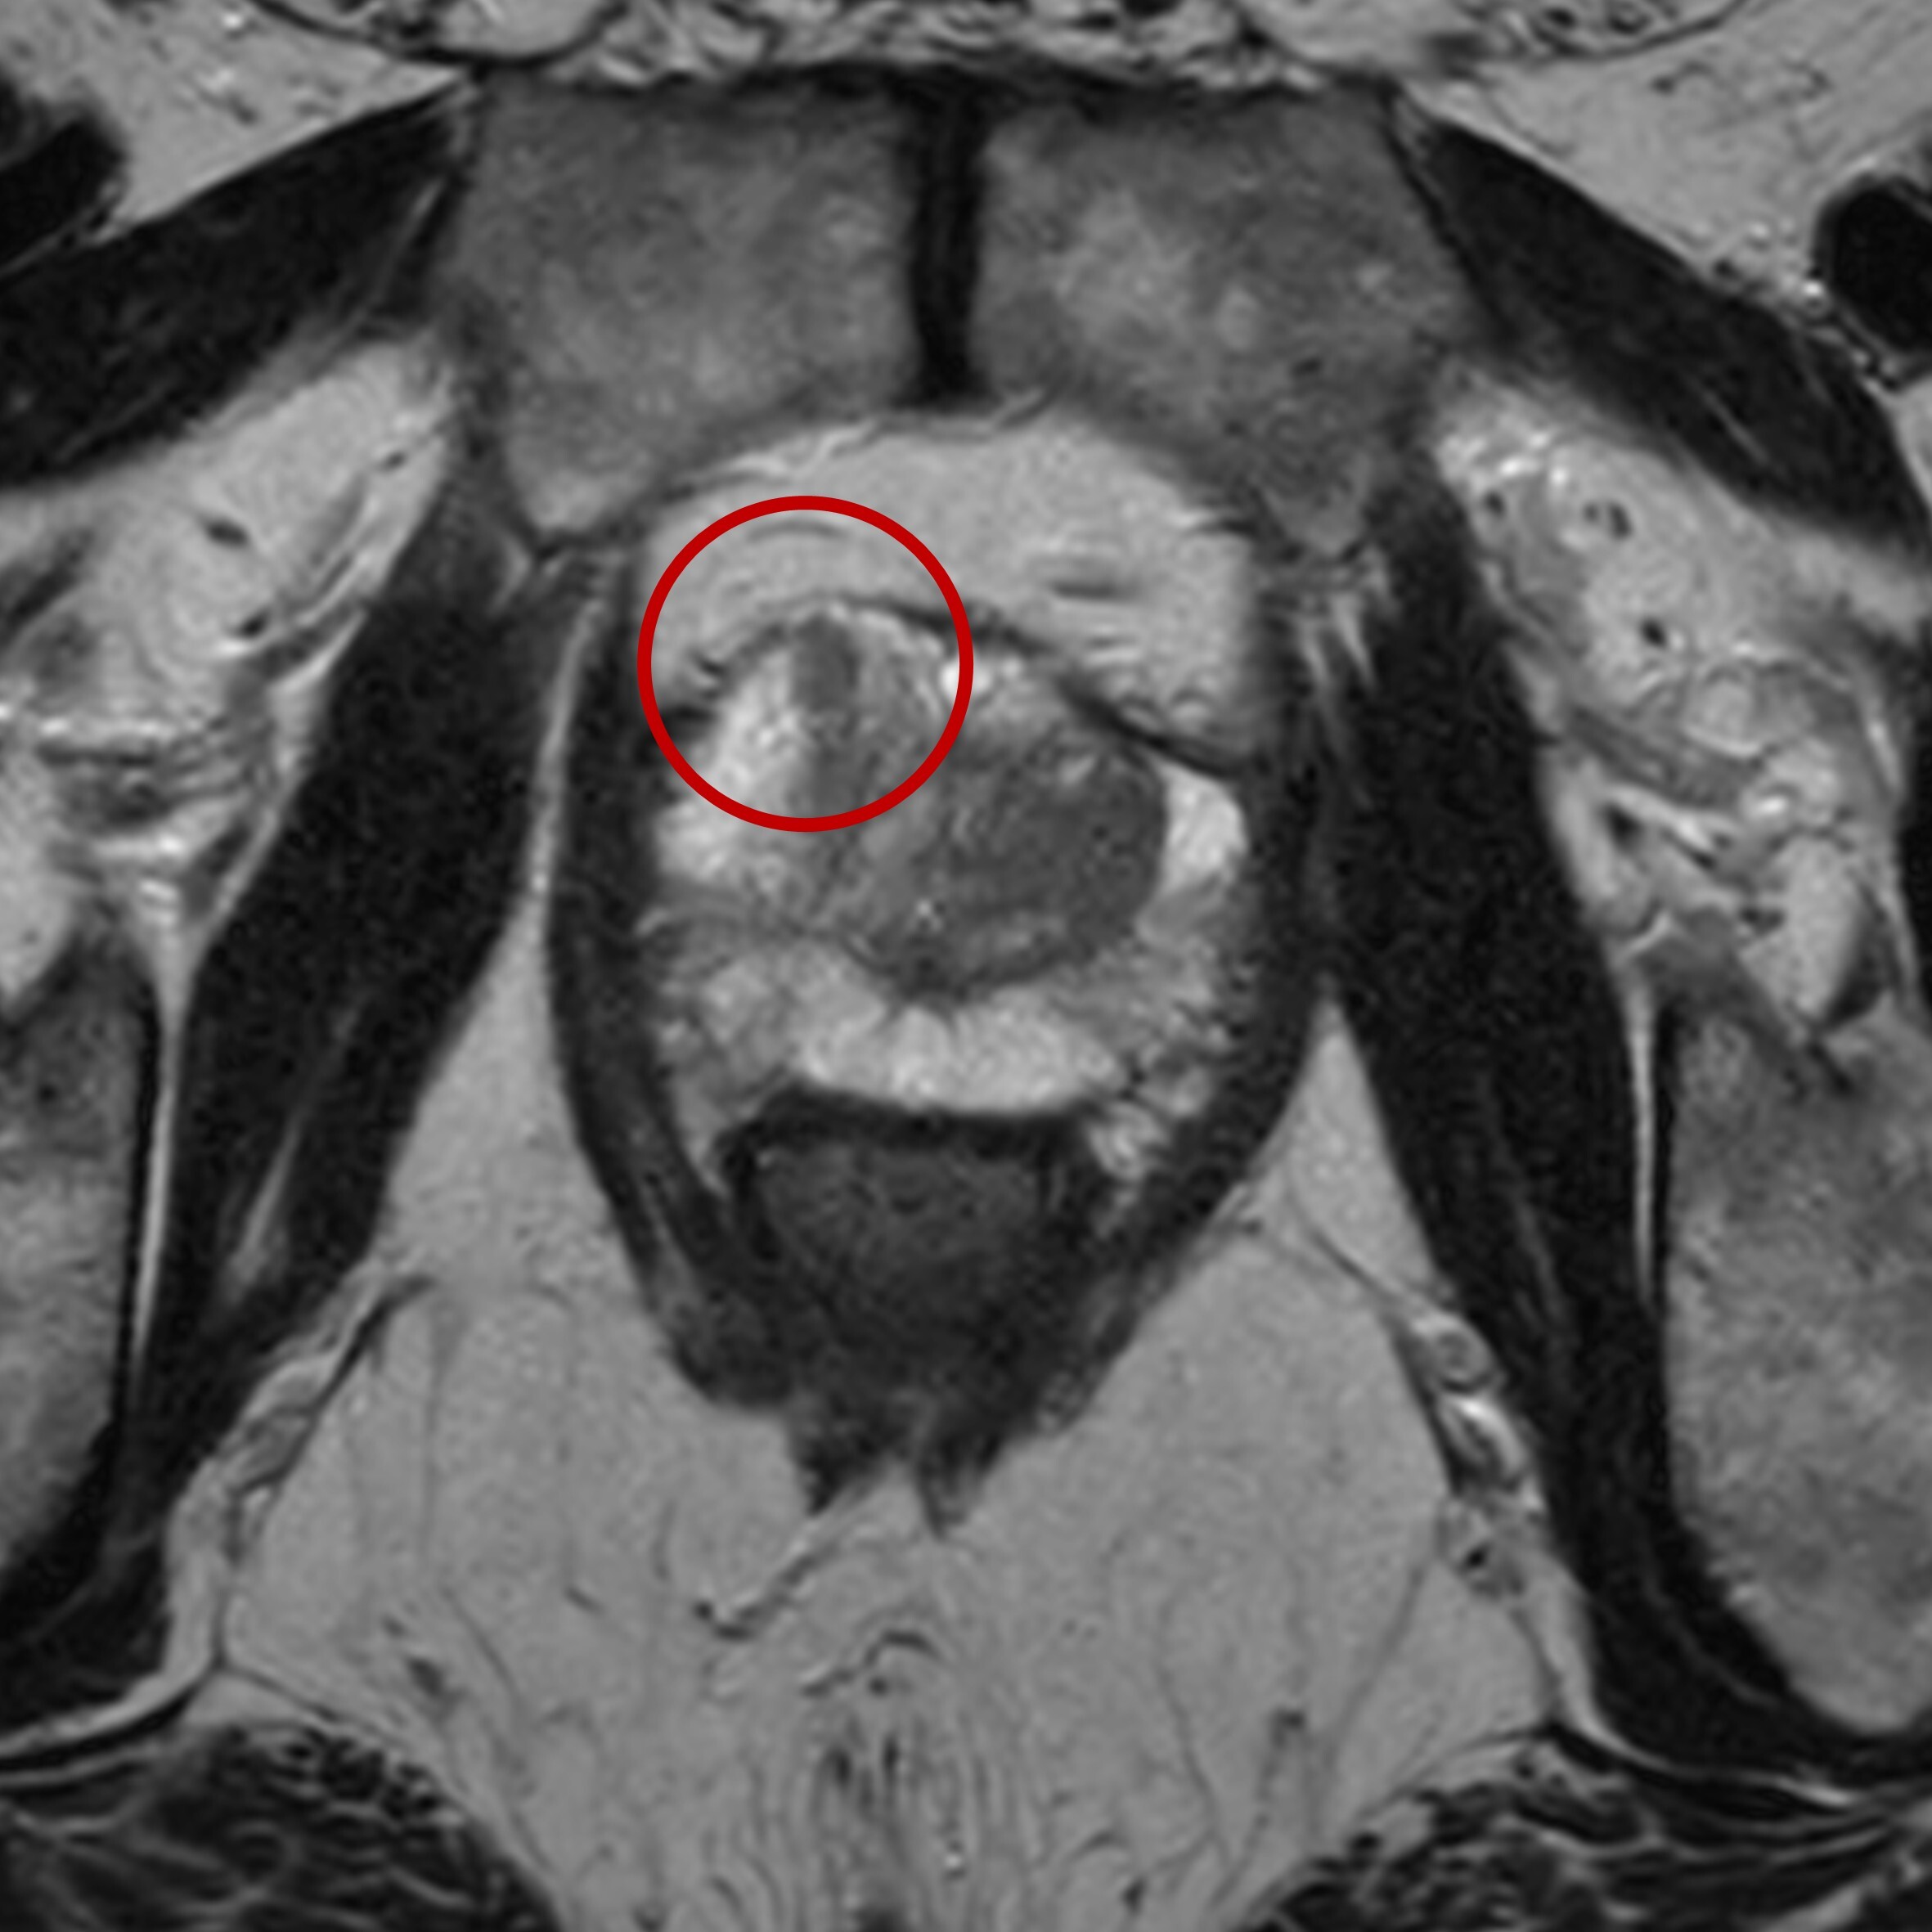

Eine kleine (<5 mm) Läsion zeigt sich in der mpMRT rechts vorne (links im Bild, roter Kreis) im sog. Vorderhorn der peripheren Zone der Prostata. In allen im Rahmen der mpMRT akquirierten Messungen (siehe oben) imponiert diese krebstypisch, aufgrund der geringen Größe zu werten als PI-RADS 4 ("bösartige Veränderungen wahrscheinlich").

Aufgrund der geringen Größe der Läsion und der etwas atypischen Lage weit vorne innerhalb der Prostata besteht ein hohes Risiko, dass solche Krebse bei Durchführung einer Biopsie ohne vorherige mpMRT verpasst werden. In Kenntnis des Befunds der mpMRT kann jedoch eine gezielte Biopsie durchgeführt werden.